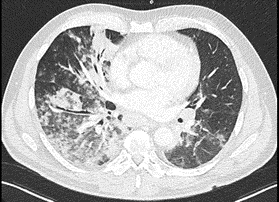

A  nasopharyngeal swab FilmArray Respiratory Panel Assay (NP FARP) was then requested: it was positive for human Metapneumovirus and the result was confirmed by repeating the test. For non responder fever and further increase of CPR (230 mg/l) and PCT (0.27 ng/ml), Levofloxacin and later Meropenem were added in the perspective of a resistant bacterial etiology.  On  the 6th hospitalization daya chest computed tomography (CT) scan was obtained (Figures 1 and 2) which demonstrated large opacities with gradient borders, distributed in the peribronchial area at the right upper lobe, middle lobe and both the lower lobes; they tended to the confluence configuring parenchymal consolidations with aerial bronchogram at the level of the cost-phrenic angle. Imaging also showed bilateral hilar and mediastinal lymphadenopathy (max diameter 3.4 x 2 cm), splenomegaly and absence of pleural effusion. Blood chemistry tests for HIV, Aspergillus antigen and galactomannan were also investigated but turned out negative. To rule out other infectious agents the patient underwent bronchoscopy with bronchoalveolar lavage (BAL) into the middle lobe. BAL provides material for various microbiological and cytological tests: Gram stain, culture, Koch’s bacillus DNA, Galactomannan, Cytomegalovirus and P. Jirovecii and immunological analysis were negative. From respiratory virus panel on BAL only human Metapneumovirus was isolated, this unique microbiological data was according to the NP FARP’s result,  thus supporting and confirming the new hypothesis of a viral pneumonia in an adult patient with probable secondary mild immunosuppression due to his hematological disease. About ten days after entering the ward, there was a gradual decrease of CPR and a progressive improvement in clinical conditions and respiratory function to allow the suspension of oxygen therapy. At the end of hospitalization, pulmonary function tests were performed and showed a restrictive syndrome (FEV1/FVC 76.2, TLC 68% and VC 79% of predicted) and mild reduction of diffusion capacity (DLCO 62% and KCO 99%), probably representing the residual functional impairment due to viral pneumonia. The patient finally suspended all therapies and at discharge was referred for a one-month follow-up visit.

Figure 1. Horizontal slice of chest CT of a hMPV pneumonia